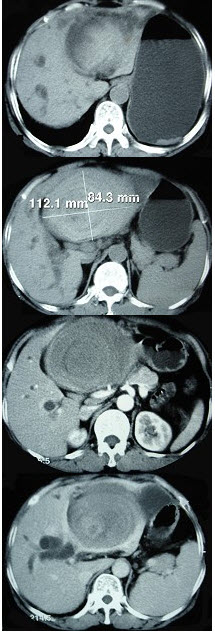

男,52岁,右上腹隐痛1年,巩膜黄染,皮肤不黄,CT检查如图,最可能的诊断为( )

A:原发性肝癌

B:肝腺瘤

C:胆管结石

D:胆管癌

E:胆囊癌